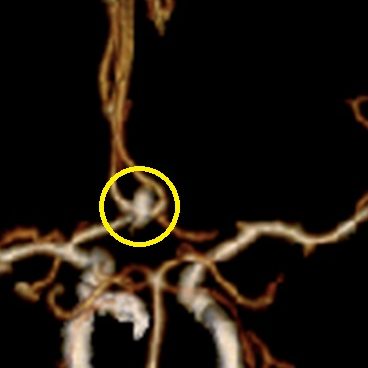

当科で治療した年々大きくなった大型脳底動脈瘤の3次元脳血管撮影像です。脳動脈瘤と周囲の血管の状態が非常によく分かるため、術前に十分な検討が可能でした。

正常の脳底動脈の血流は維持されている。